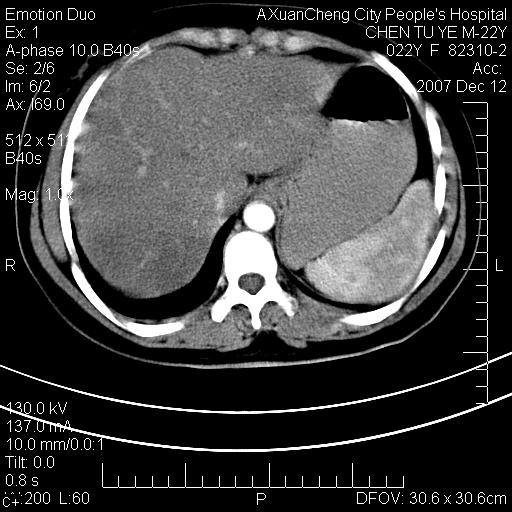

超声提示肝右前叶占位,约2.5cm.

各位战友看看病灶在什么地方,可是右前叶进肝裂部低密度影,平扫ct值约10以下,增强后增高明显

1 脾大,慢性肝损伤. 2 肝脏脂肪侵润.  3 你所指的部位疑点,我没看出有问题.

1 脾大,慢性肝损伤. 2 肝脏脂肪侵润.

脂肪肝,脾大

重度脂肪肝.